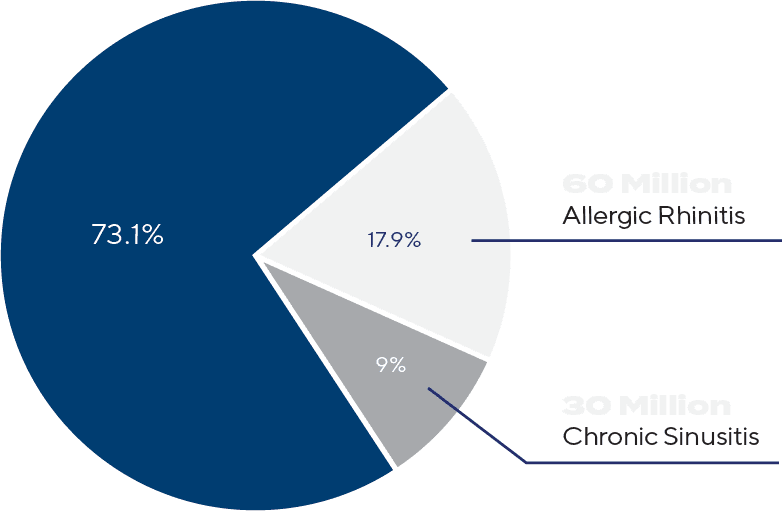

Prevalence in the United States

Allergic Rhinitis & Chronic Sinusitis

The Burden of Nasal Inflammation — and the Opportunity for Better Relief

Over 60 million Americans suffer from allergic rhinitis and another 30 million from chronic sinusitis, representing nearly one in four U.S. adults. As shown, allergic rhinitis accounts for 17.9% and chronic sinusitis for 9% of the population — together comprising an enormous and overlapping patient group struggling with nasal inflammation, congestion, and impaired quality of life. Yet, despite the prevalence, current treatments such as sprays and pills often provide incomplete relief because they fail to reach the entire nasal cavity and sinus cavities where inflammation persists. RhineX was designed to address this unmet need — an ENT-engineered, steroid-enhanced nasal rinse that delivers medication where it’s needed most. This large and underserved market represents a significant opportunity to improve outcomes for millions of patients seeking better breathing and lasting relief.